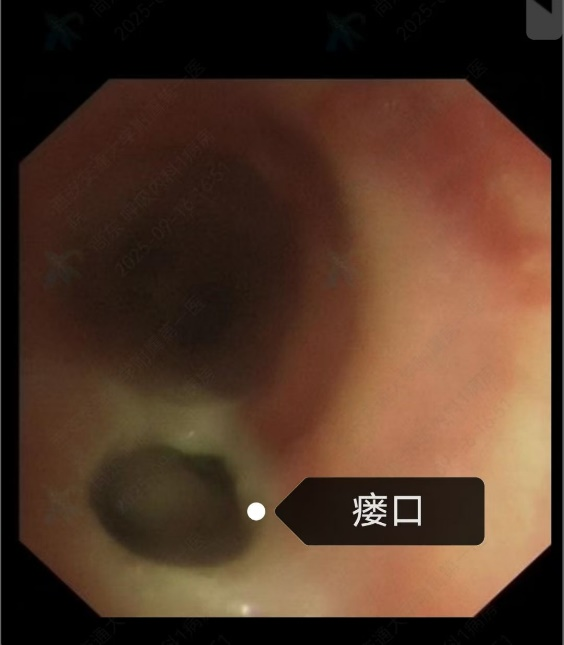

今年 9 月,赵阿姨有强烈的取出支架意愿,遂入住东院区呼吸与危重症医学科。入院后影像学提示其气管食管瘘口已基本愈合,具备取出支架的条件,但动态心电图仍显示频发室早,室早二联律,麻醉风险较高。为保障赵阿姨是安全,科室迅速启动多学科协作(MDT)机制,联合麻醉手术部、心血管内科、医学影像科、胸部外科专家进行全面讨论。经充分评估,最终制定手术方案:术前先行「左侧星状神经节阻滞术」改善心律失常,为后续麻醉及手术创造条件。

9 月 16 日,在东院区副院长、麻醉手术部主任高巍,副主任医师庞芸全程监护下,尚东主任带领团队成功为赵阿姨施行「硬质气管镜下硅酮支架取出术」。术中仔细清理支架周围感染灶及增生肉芽,完整取出留置两年之久的支架,并确认瘘口愈合良好,手术过程顺利,生命体征平稳。